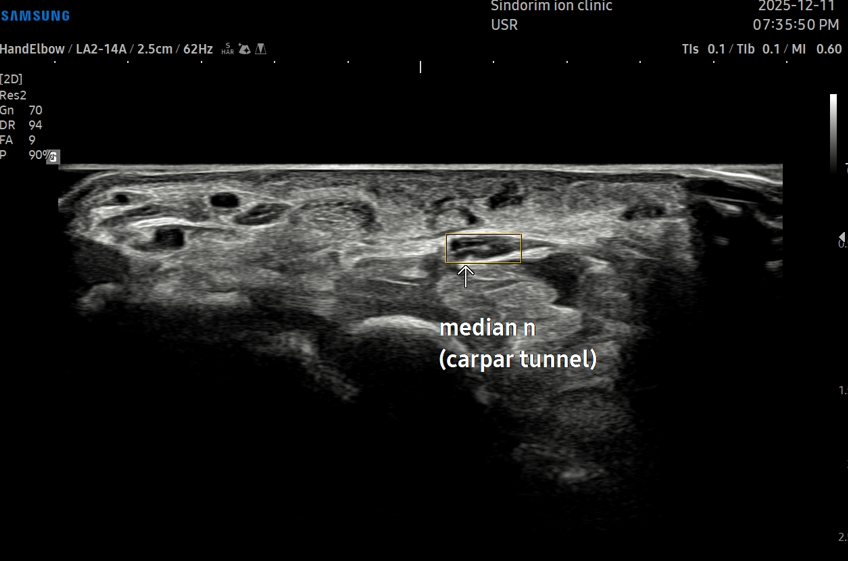

- 치료기간 : 25 . 8 . 19 ~ 25 . 10 .24

- 치료횟수 : 11 회(아피톡신+극초단파)

마지막 치료 이후 내원이 어려우셔서 유선상 확인